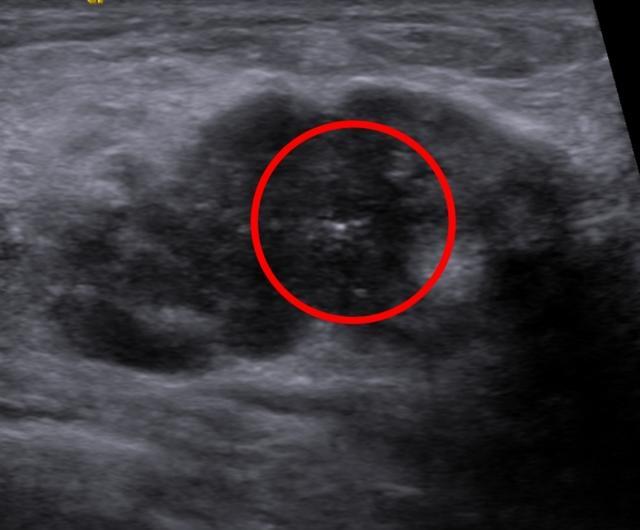

右乳肿块超声结果显示:

超声所见:右乳低回声结节,形态不规则,边界不清,边缘成角,呈“蟹足样”改变,可见多个微钙化。

结合女士乳腺超声声像图改变,诊断如下:右乳10点低回声结节,BI-RADS4c类;右乳多发低回声结节,BI-RADS4a类;右侧腋窝多发异常淋巴结声像;